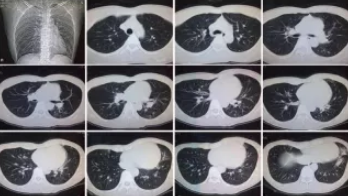

CT檢查原理是X光分層穿過(guò)人體,這就像把面包切成薄片,每一片都可以攤開(kāi)看。當(dāng)遇到外傷懷疑傷到骨頭,可以選擇CT觀察隱匿損傷或軟組織損傷。

CT適用于頭部、胸部、腹部、盆腔、脊柱、四肢、骨骼等處,由于它的特殊診斷價(jià)值,已經(jīng)廣泛應(yīng)用于臨床,特別是在腫瘤的診斷上更是具有很高的應(yīng)用價(jià)值。但由于CT設(shè)備較為昂貴,檢查費(fèi)用也會(huì)偏高,對(duì)于某些部位的檢查和診斷價(jià)值,尤其是定性診斷,還有一定限度,所以在臨床上并沒(méi)有將CT檢查視為常規(guī)診斷手段。此外,CT診斷輻射量大于DR,所以懷孕或備孕期女性不宜進(jìn)行CT檢查。